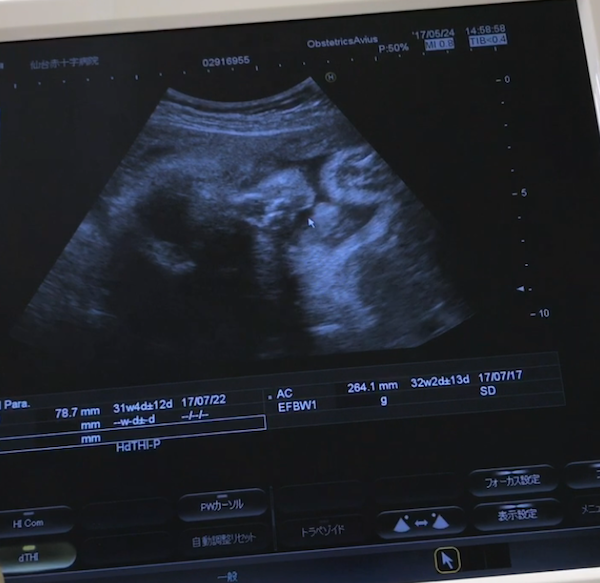

23週3日(23w3d・男の子)|てんちゃんまんま さん(30歳)

エコー写真撮影時のエピソード:

先生が大腿骨を測っていた時に「ここ、おまたですか?女の子ですかね~?」と聞いたら、ぐりぐりとよく調べてくれました。その途端ばっちり股間に男の子の印が見えました。

ずっと上の子が、赤ちゃんは女の子だと言っていたので、女の子だと思っていたのでびっくり!一緒に見ていた上の子も「え?!男の子なの?」とぽかーん!